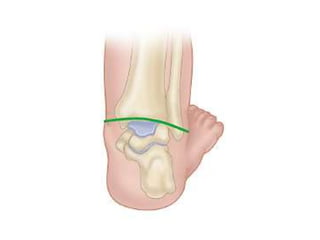

Kinematics

• Talus: most deformed and least displaced.

Head & neck deviated medially & plantarward

Body rotated externally in the ankle mortise,

superior articular surface escapes from mortice.

Talar neck is short and medially deviated.

Smaller than normal, disturbance of vascular

supply, ossification centre eccentrically placed.

• Navicular:

Medially displaced

Close to medial malleolus

Articulates with medial surface of head of talus

• calcaneus is

– adducted and

– inverted under the talus

• Cuboid

Displaced medially on the dysmorphic distal end

of the calcaneus

Tibio-talar plantar flexion

Medially displaced navicular

Adducted and inverted

calcaneus

Medially displaced

cuboid

• Correction of the extreme medial

displacement and inversion of the tarsal

bones in the clubfoot necessitates a

simultaneous gradual lateral shift of the

navicular, cuboid, and calcaneus before they

can be everted into a neutral position